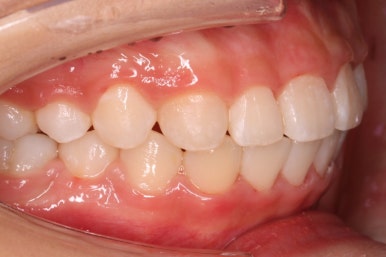

치료 종료 후의 모습입니다.

치아들이 가지런하게 되었고, 나오지 못하던 치아도 잘 나와서 가지런해졌습니다.

해당 부위 앞뒤로 쓰러져 있던 치아들도 축이 바로 잡혔고, 자연스레 위-아래 치아의 중앙선도 맞아졌습니다.

부산치아교정잘하는곳 키다리아저씨치과에서 이번 청소년 환자분께 치료하느라 소요된 기간은 총 16개월이였습니다.